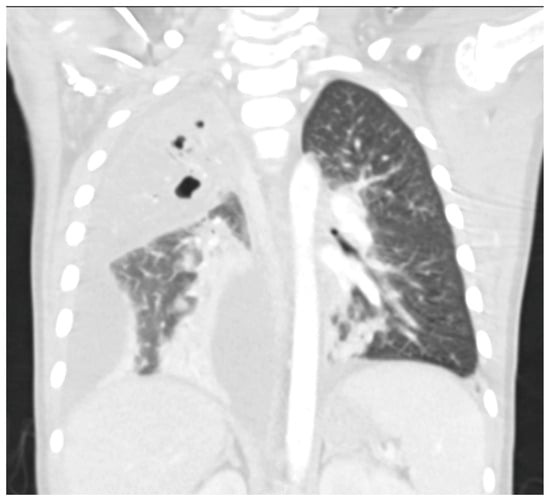

- Hoffer, F.; Bloom, D.; Colin, A.A.; Fishman, S.J. Lung abscess versus necrotizing pneumonia: Implications for interventional therapy. Pediatr. Radiol. 1999, 29, 87–91. [Google Scholar] [CrossRef]

- Hodina, M.; Hanquinet, S.; Cotting, J.; Schnyder, P.; Gudinchet, F. Imaging of cavitary necrosis in complicated childhood pneumonia. Eur. Radiol. 2002, 12, 391–396. [Google Scholar] [CrossRef][Green Version]

- Carrard, J.; Bacher, S.; Rochat-Guignard, I.; Knebel, J.-F.; Alamo, L.; Meuwly, J.-Y.; Tenisch, E. Necrotizing pneumonia in children: Chest computed tomography vs. lung ultrasound. Front. Pediatr. 2022, 10, 898402. [Google Scholar] [CrossRef]